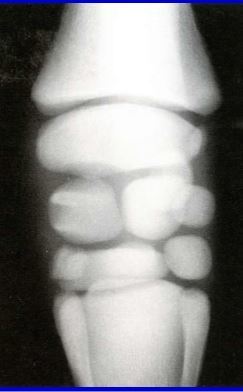

On rads of a foal’s joint you note that the carpal bones appear rounded. What does this indicate and what conditions can this lead to?

A

Incomplete ossification

Vargus or valgus or ligament laxity (leading to deformity)